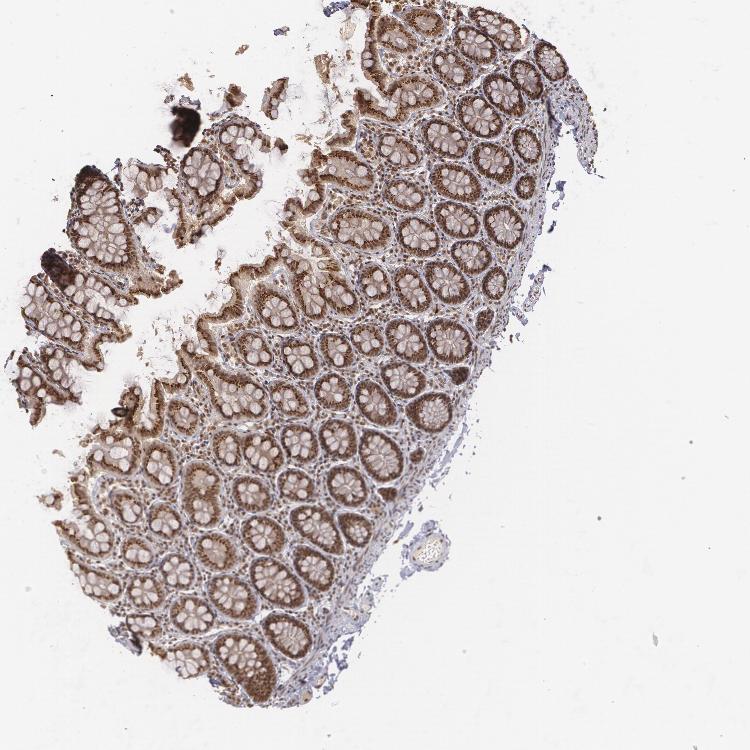

COLON - Antibody stainingi

Antibody staining in the annotated cell types in the current human tissue is reported as not detected, low, medium, or high, based on conventional immunohistochemistry profiling in selected tissues. This score is based on the combination of the staining intensity and fraction of stained cells.

Each image is clickable and will lead to virtual microscopy that enables deeper exploration of all samples and also displays staining intensity scores, fraction scores and subcellular localization as well as patient and tissue information for each sample.

Antibody CAB002003

Endothelial cells Medium

Glandular cells High

Peripheral nerve/ganglion Medium